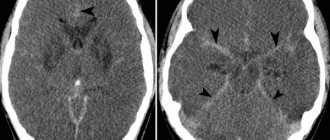

Информативна ли МСКТ сосудов мозга при фузиморфной аневризме

• Трубчатая гиперденсная структура в типичном месте

• Веретенообразная аневризма базилярной артерии: предмостовая локализация

• Веретено­образная аневризма средней мозговой артерии: сильвиева борозда

• Обыз­вествление стенки сосуда

• Значительное усиление после введения КС (КТ-ангиография).